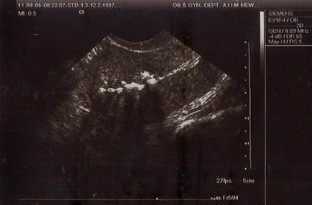

Fig. 2